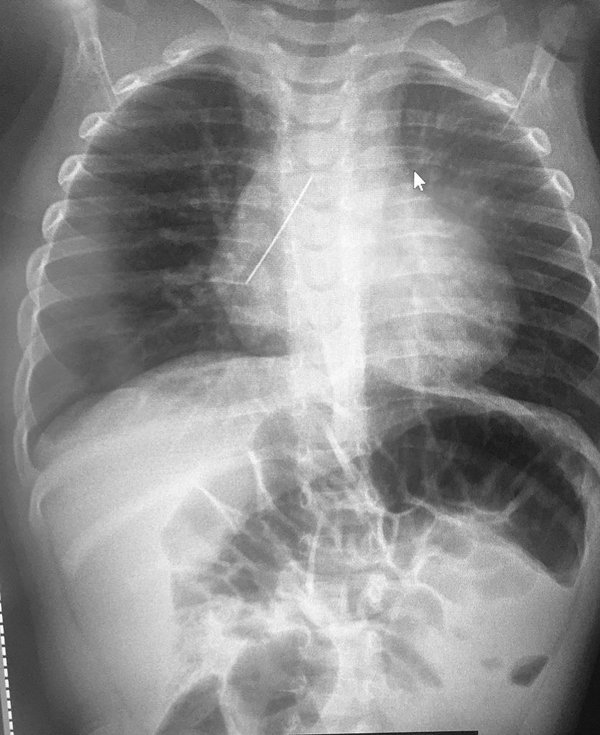

Las que utilizan Rayos X (Radiografía, Mamografía, Urografía, TAC, PET TC, Acelerador de Radioterapia) atraviesan nuestro cuerpo e impactan sobre un detector situado al otro lado de nuestro cuerpo. La radiación ionizante pasan por nuestros tejidos proyectando una imagen. Pero no atraviesan metal, que además distorsiona o emborrona los bordes de todo lo que rodea, y por tanto produce artefactado. Existen pacientes que ya llevan metal dentro de su cuerpo como por ejemplo prótesis de cadera, implantes dentales, marcapasos… que no podemos ‘evitar’ en la imagen.

Elementos ‘prohibidos’: Pero el paciente debe entender que todo elemento metálico no deja pasar la radiación. Existen también otros elementos que dejan pasar la radiación pero producen un efecto no deseable en la imagen, porque puede ‘simular’ una imagen patológica: cosas con hueso, plásticos muy gruesos, cosas con cuero o pelo muy atado… Típicos de las joyas y de abalorios o piercing. Bolígrafos en una camisa, monedas, anillos, pulseras, tarjetas electrónicas (por el plástico y la banda magnética, que puede sufrir daños), cinturones, metales del pantalón, reloj, pinzas y otras cosas en el pelo, pendientes, collares … y las típicas faldas con cremallera o enganches, fajas y sujetadores con elementos metálicos o con plástico duro (comprobar las dos radiografías del inicio de este artículo). Y también la madera puede distorsionar la imagen.

Lo cierto es que si se hace una radiografía y aparece un metal (como un sujetador) no le va a afectar a su organismo de forma directa. Pero si hay que repetir la prueba entonces se ‘dobla’ la radiación ionizante que tendría que haber recibido. ¿Por qué hay que repetir? Porque un metal, o un plástico duro o botón, o una pulsera de cuero, o algo de hueso (dientes o perlas) pueden ‘tapar’ o simular una patología. Y entonces, Ud. se hace la prueba y por culpa de ese elemento no se puede diagnosticar con precisión esa patología que podría haberse visto sin ‘obstáculos’.